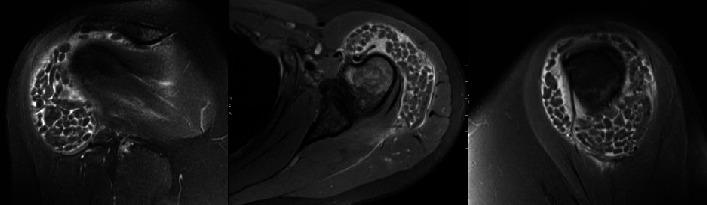

Rice bodies (RBs) are pale and glossy appearing small fibrinous nodules that form due to synovial or tenosynovial joint inflammation. RBs are significant as they are common in orthopedic practices causing nonspecific symptoms such as pain, swelling, range of motion limitations, crepitus, and catching sensations. These loose bodies occur often within the bursa as a symptom of chronic bursitis and are commonly associated with rheumatoid, inflammatory, or tuberculous arthritis. Reports on RBs are present; however, few bilateral cases within the shoulder appear in the literature. . This case demonstrates an unusual bilateral, subacromial-subdeltoid presentation of rice bodies (RBs) in a 41-year-old Caucasian female patient with a history of rheumatoid arthritis. We describe treatment with right shoulder arthroscopy to remove the loose bodies. One-year postoperative patient-reported outcomes (PROMs) show improvement in symptoms, pain, and overall function.

米粒体(RBs)是苍白且有光泽的小纤维性结节,由滑膜或腱鞘关节炎症形成。米粒体很重要,因为它们在骨科临床中很常见,会引起疼痛、肿胀、活动范围受限、摩擦音和卡顿感等非特异性症状。这些游离体常出现在滑囊内,是慢性滑囊炎的症状,通常与类风湿性、炎症性或结核性关节炎有关。关于米粒体的报道已有;然而,文献中很少有肩部双侧病例。本病例展示了一名41岁有类风湿关节炎病史的白种女性患者出现不寻常的双侧肩峰下-三角肌下米粒体(RBs)表现。我们描述了通过右肩关节镜手术切除游离体的治疗方法。术后一年患者报告的结果(PROMs)显示症状、疼痛和整体功能有所改善。